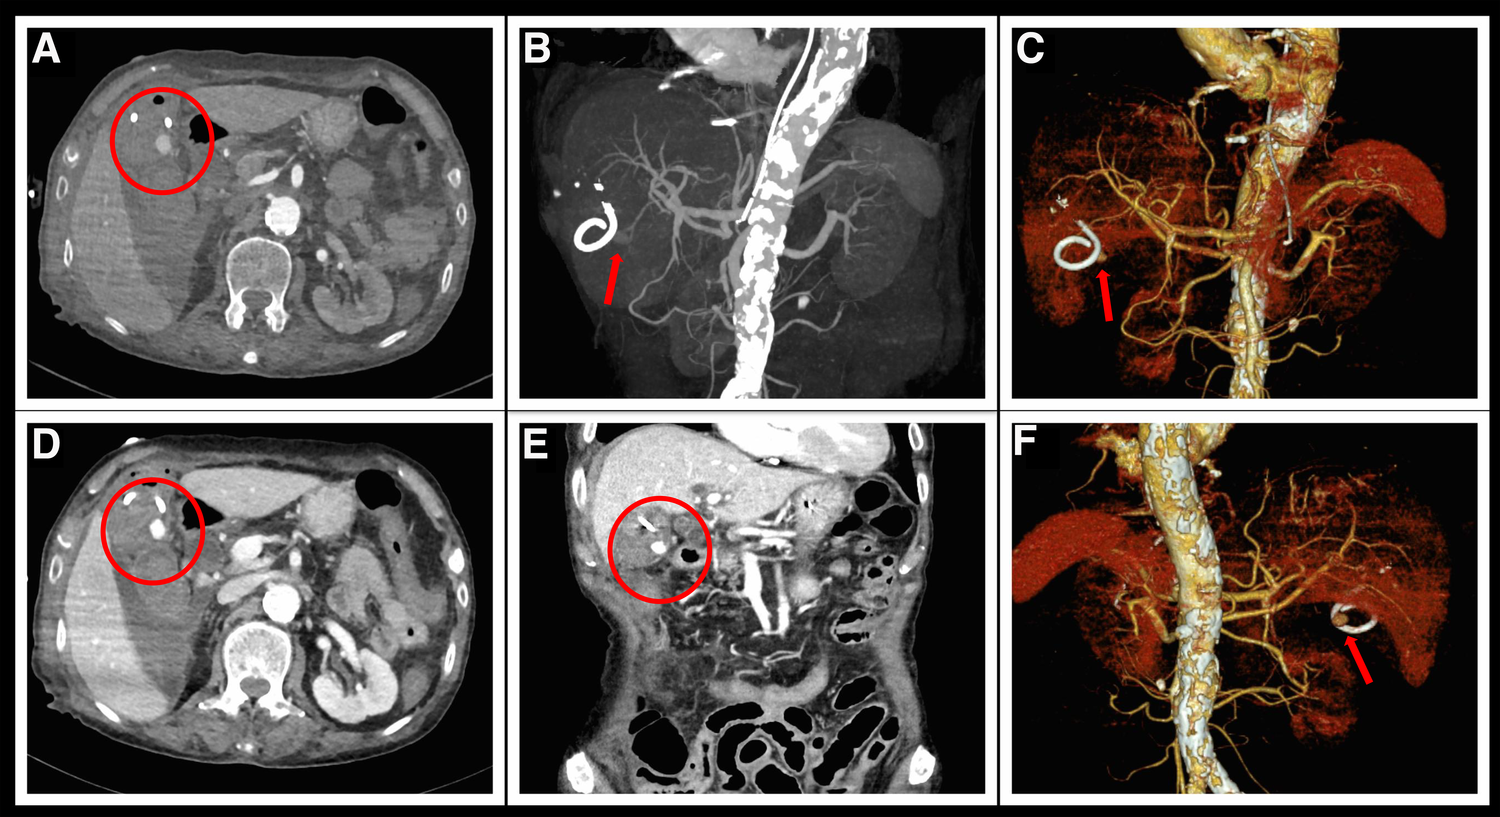

Figure 3

Aortic CTA examination after hematemesis. (A,D) Delayed enhancement of the pseudoaneurysm of the gallbladder artery (encircled in red) during the arterial phase of CTA. (B,C,E,F) Reconstructed three-dimensional images clearly show a spherical pseudoaneurysm at the exit of the gallbladder artery. (E) Reconstructed coronal section image shows an enhanced pseudoaneurysm image below the gallbladder.

After the cessation of hemoptysis, the patient developed severe right upper abdominal pain and recurrently vomited fresh blood. Emergency abdominal CT scan revealed acute cholecystitis with biliary bleeding (Figure 1F). With the assistance of interventional doctors, percutaneous cholecystocentesis and drainage were performed, resulting in the extraction of approximately 150 ml of bloody fluid. To identify the cause of abdominal pain and vomiting, we conducted computed tomography angiography (CTA) of the entire aorta, which revealed a newly formed pseudoaneurysm in the gallbladder artery (Figure 3).